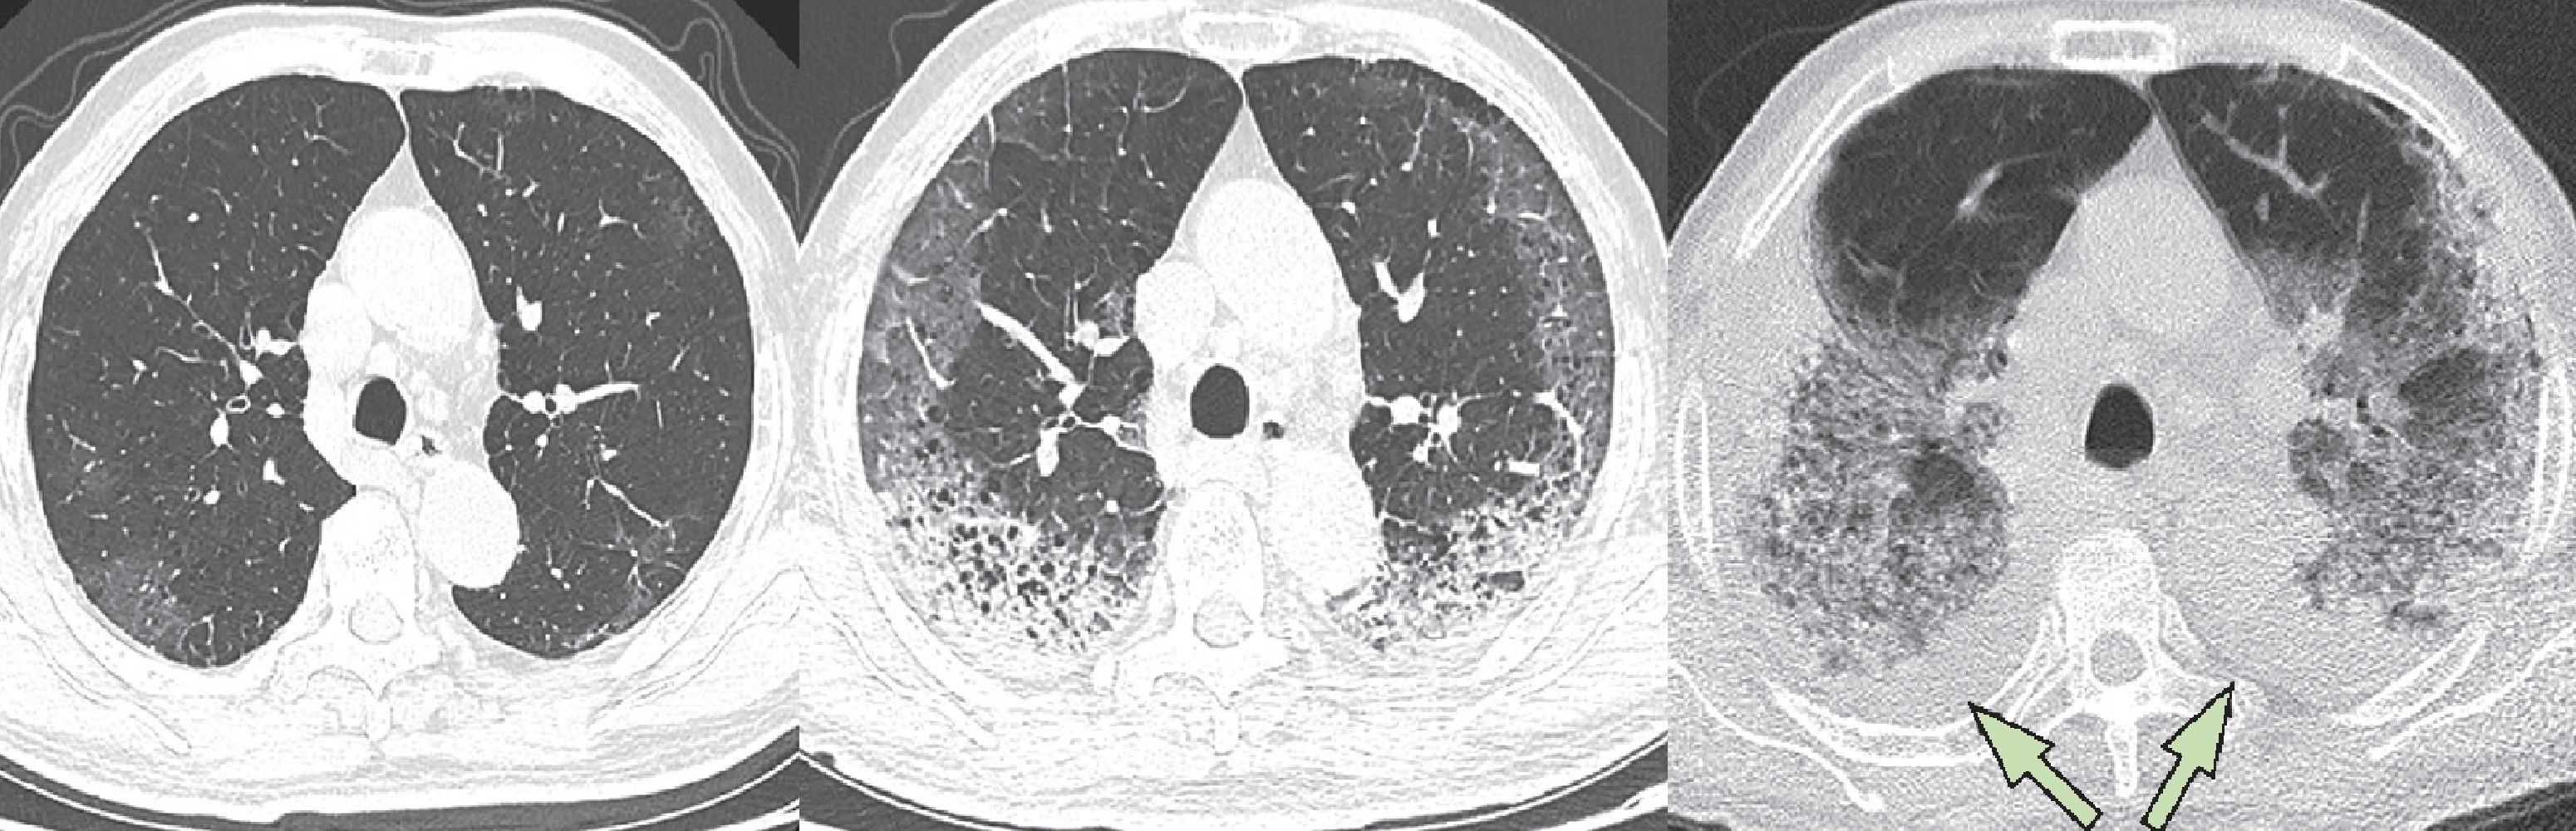

Фото рентгеновских снимков поражения легких при COVID-19

На фотографиях рентгеновских снимков видно, как вирус воздействует на легочную ткань. Характерные признаки поражения легких включают пятна, инфильтраты и наличие жидкости внутри легочных альвеол.

Фото рентгеновских снимков помогают врачам и специалистам визуально определить степень поражения легких и принять соответствующие меры лечения и поддержки пациента.